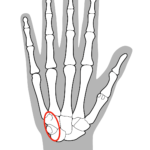

小指側にある尺骨神経が手首の尺骨神経管(ギヨン管)の中で

締め付けられたり、圧迫を受けると尺骨神経沿いに症状があらわれます

⭕️の位置が尺骨神経の通り道です

この部分が圧迫を受けると腱鞘炎になります